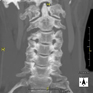

Prova radiològica que consisteix en obtenir imatges de les cervicals vertebrals d'alta definició anatòmica, mitjançant l'ús d'un equip de TC (Tomografia Computeritzada). Indicacions: cervicàlgia amb/ sense irradiació a braços, traumatisme.

Prueba radiológica que consiste en obtener imágenes de las vértebras cervicales de alta definición anatómica mediante el empleo de un equipo de TC (Tomografía Computarizada). Indicaciones: dolor cervical sin/con irradiación a brazos, traumatismo, malformaciones congénitas. - TC Columna dorsal